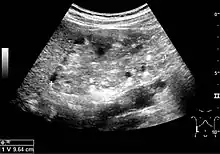

US is useful for diagnostic and prognostic purposes in chronic kidney disease. Whether the underlying pathologic change is glomerular sclerosis, tubular atrophy, interstitial fibrosis or inflammation, the result is often increased echogenicity of the cortex. The echogenicity of the kidney should be related to the echogenicity of either the liver or the spleen (Figure 22 and Figure 23). Moreover, decreased renal size and cortical thinning are also often seen and especially when disease progresses (Figure 24 and Figure 25). However, kidney size correlates to height, and short persons tend to have small kidneys; thus, kidney size as the only parameter is not reliable.[1]

Figure 25. End-stage chronic kidney disease with increased echogenicity, homogenous architecture without visible differentiation between parenchyma and renal sinus and reduced kidney size. Measurement of kidney length on the US image is illustrated by ‘+’ and a dashed line.[1]